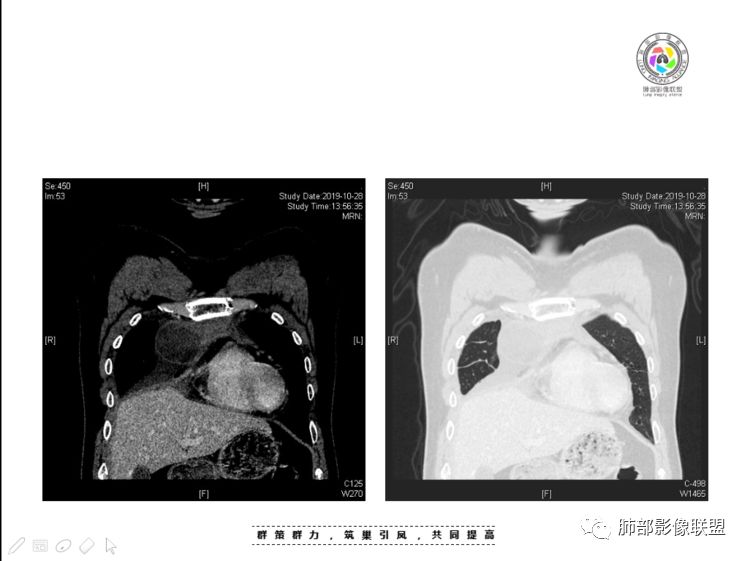

本例纵隔与肺内两处病变,回顾总结分析:

2、前纵隔内病灶囊实性混杂密度病灶,囊性病灶主要位于右侧,张力较高,有分隔影,囊壁右侧缘光整,病灶左侧实性部分边界不清明显强化,病灶肺瘤交界面大部分边界清楚,部分模糊。

前纵隔肿块伴囊变坏死常见以有胸腺瘤、胸腺癌、淋巴瘤和生殖细胞肿瘤。

纵隔内病灶不符合肺癌转移途径,且纵隔内单发的囊实性转移罕见。淋巴瘤无论是分布、形态、密度、还是强化方式度不符合。

胸腺瘤/胸腺癌符合吗?

胸腺瘤/胸腺癌:病灶内那么大的囊,常规考虑B型以上胸腺瘤,囊内有分隔影,病灶周围脂肪间隙模糊,常规考虑侵袭性胸腺瘤或胸腺癌,若侵袭性胸腺瘤,常侵犯胸膜、心包,很少累及肺。胸腺癌易侵犯胸膜、肺并纵隔淋巴结及远处转移。但肺内腺癌形态更符合原发灶。胸膜及叶间裂转移则即可来自肺,也可来自胸腺癌。

尽管前纵隔病灶缺乏相关病理资料,但是小编还是认为肺内与纵隔病灶以二元论解释。只是肺内恶性病灶引发的胸膜改变可能会影响我们对纵隔病灶的判断。